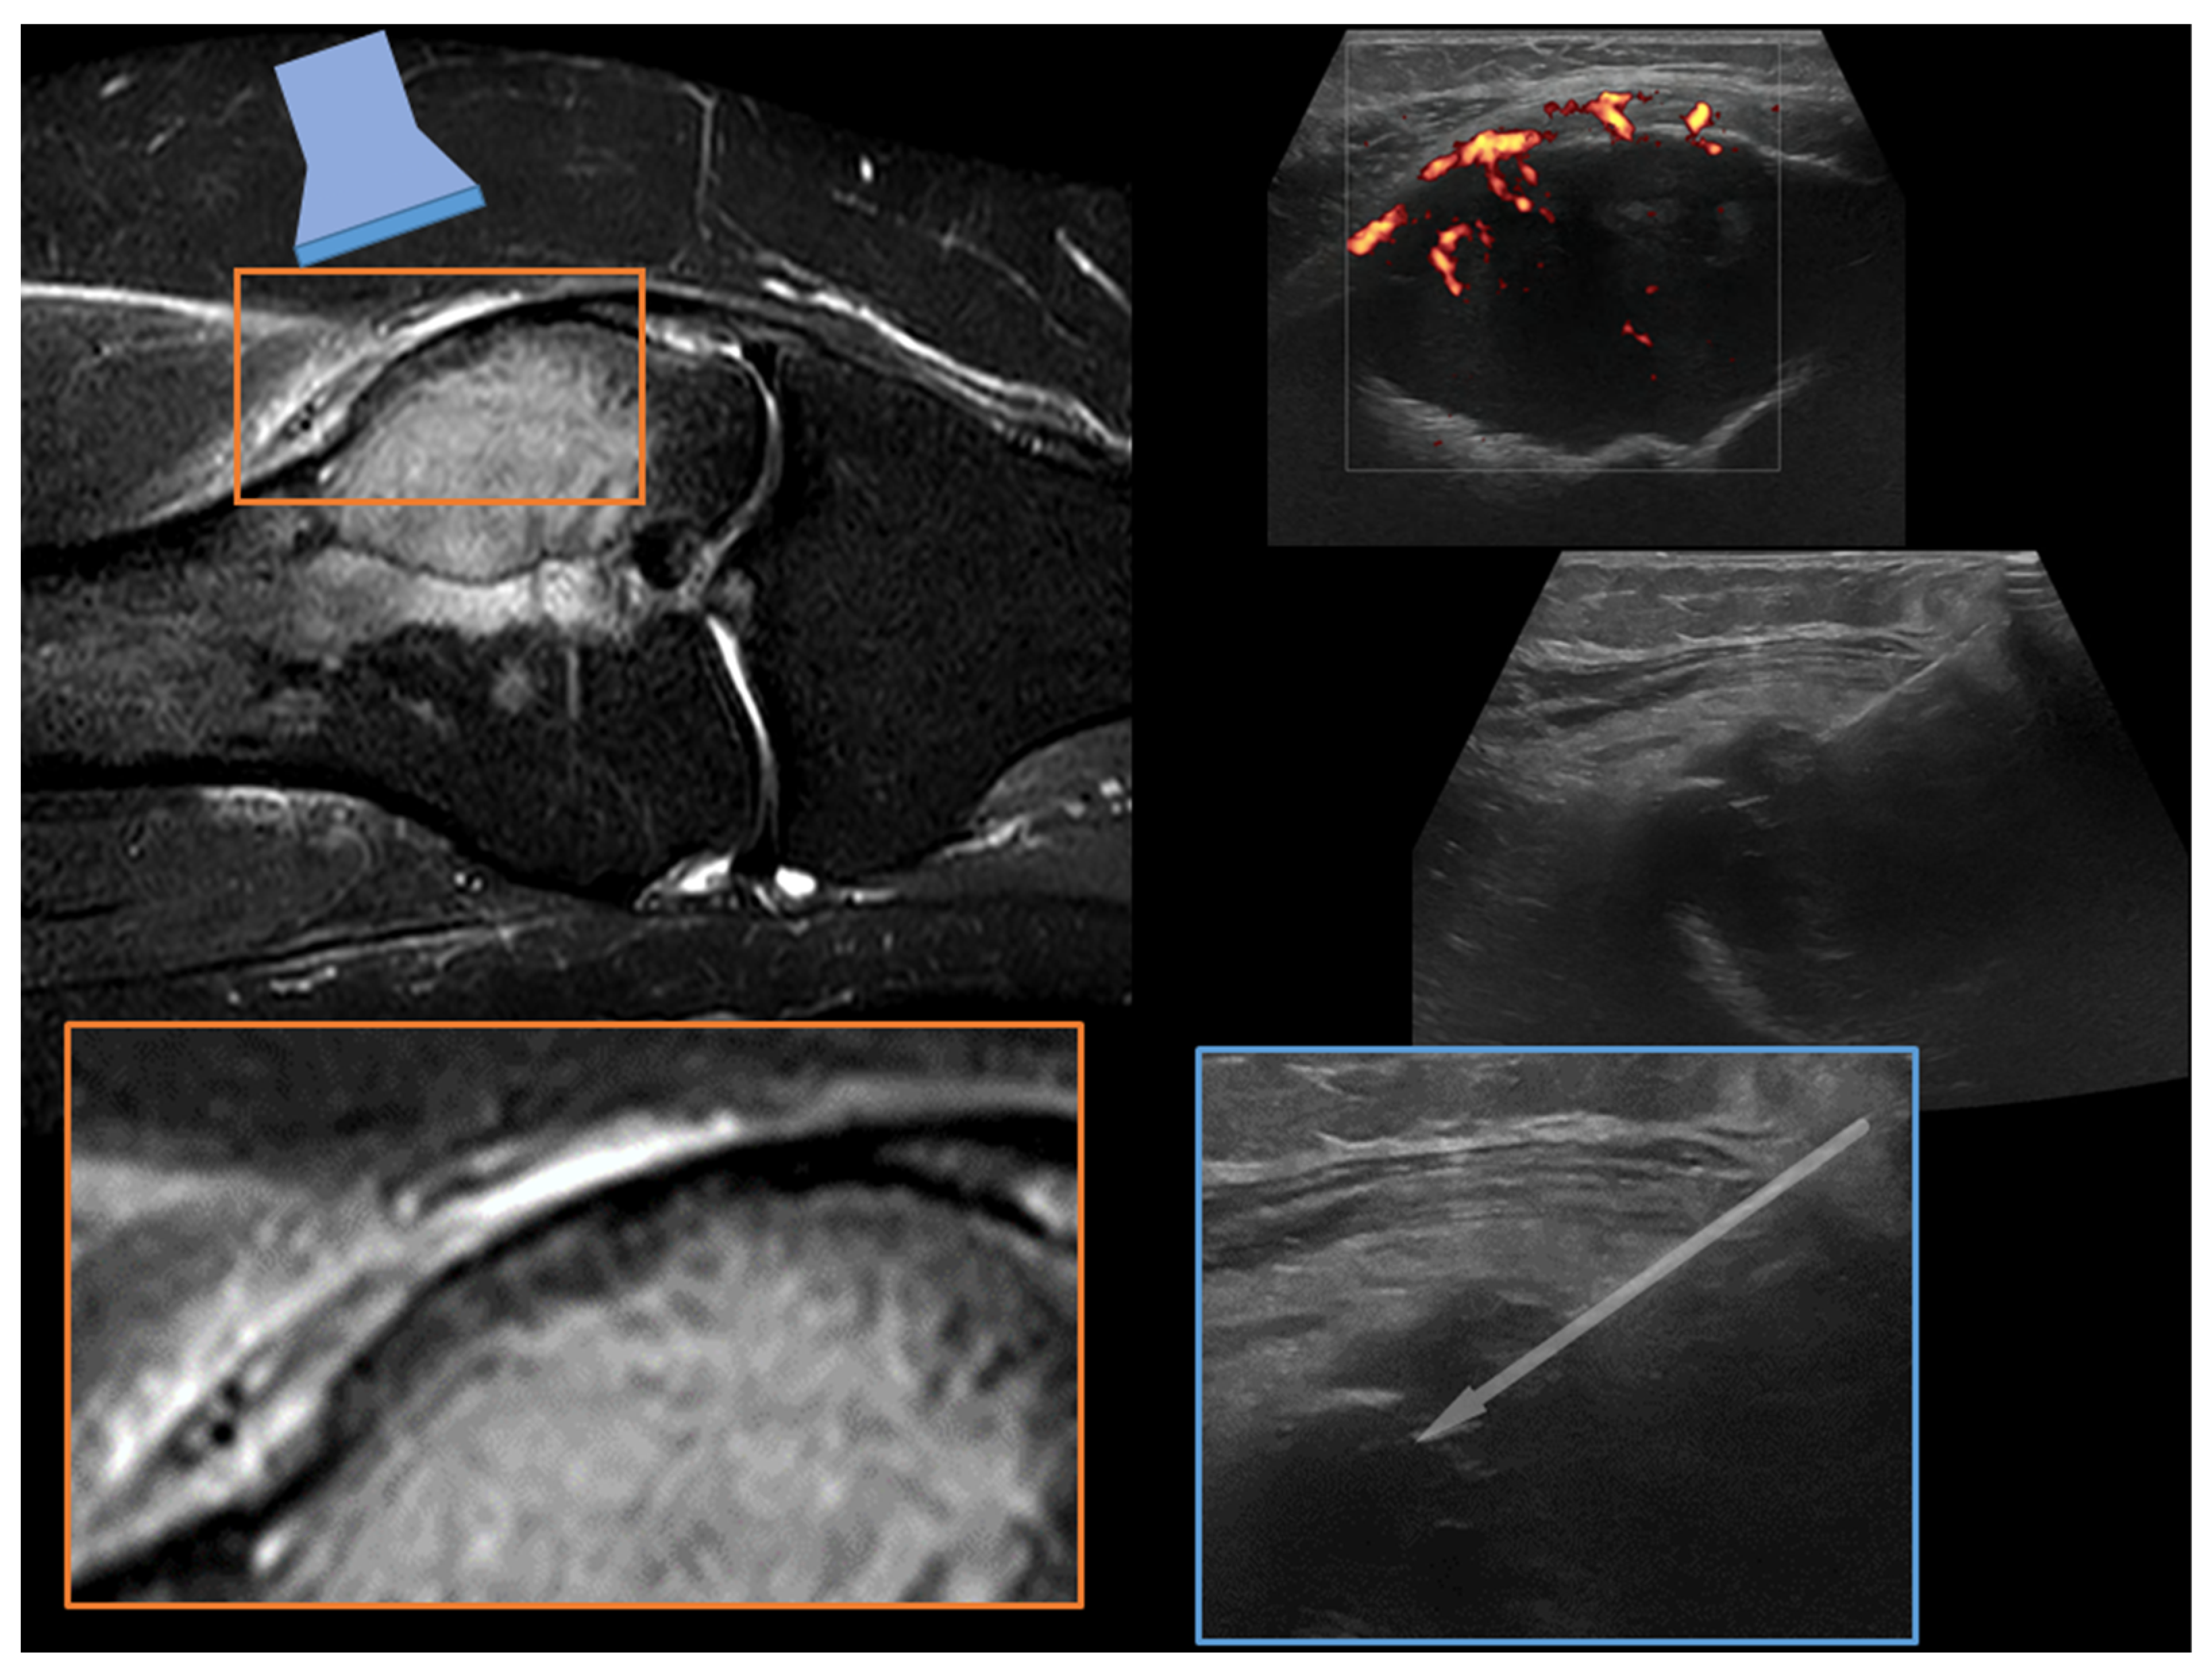

1.1. Percutaneous Bone Biopsy: General Indications

1.2. Imaging Guidance for Percutaneous Bone Biopsy

2. Technical Notes and Overview of Approaches

3.2.2. Needle Approaches and Cores

3.2.4. Target Lesion Location and Hybrid Techniques